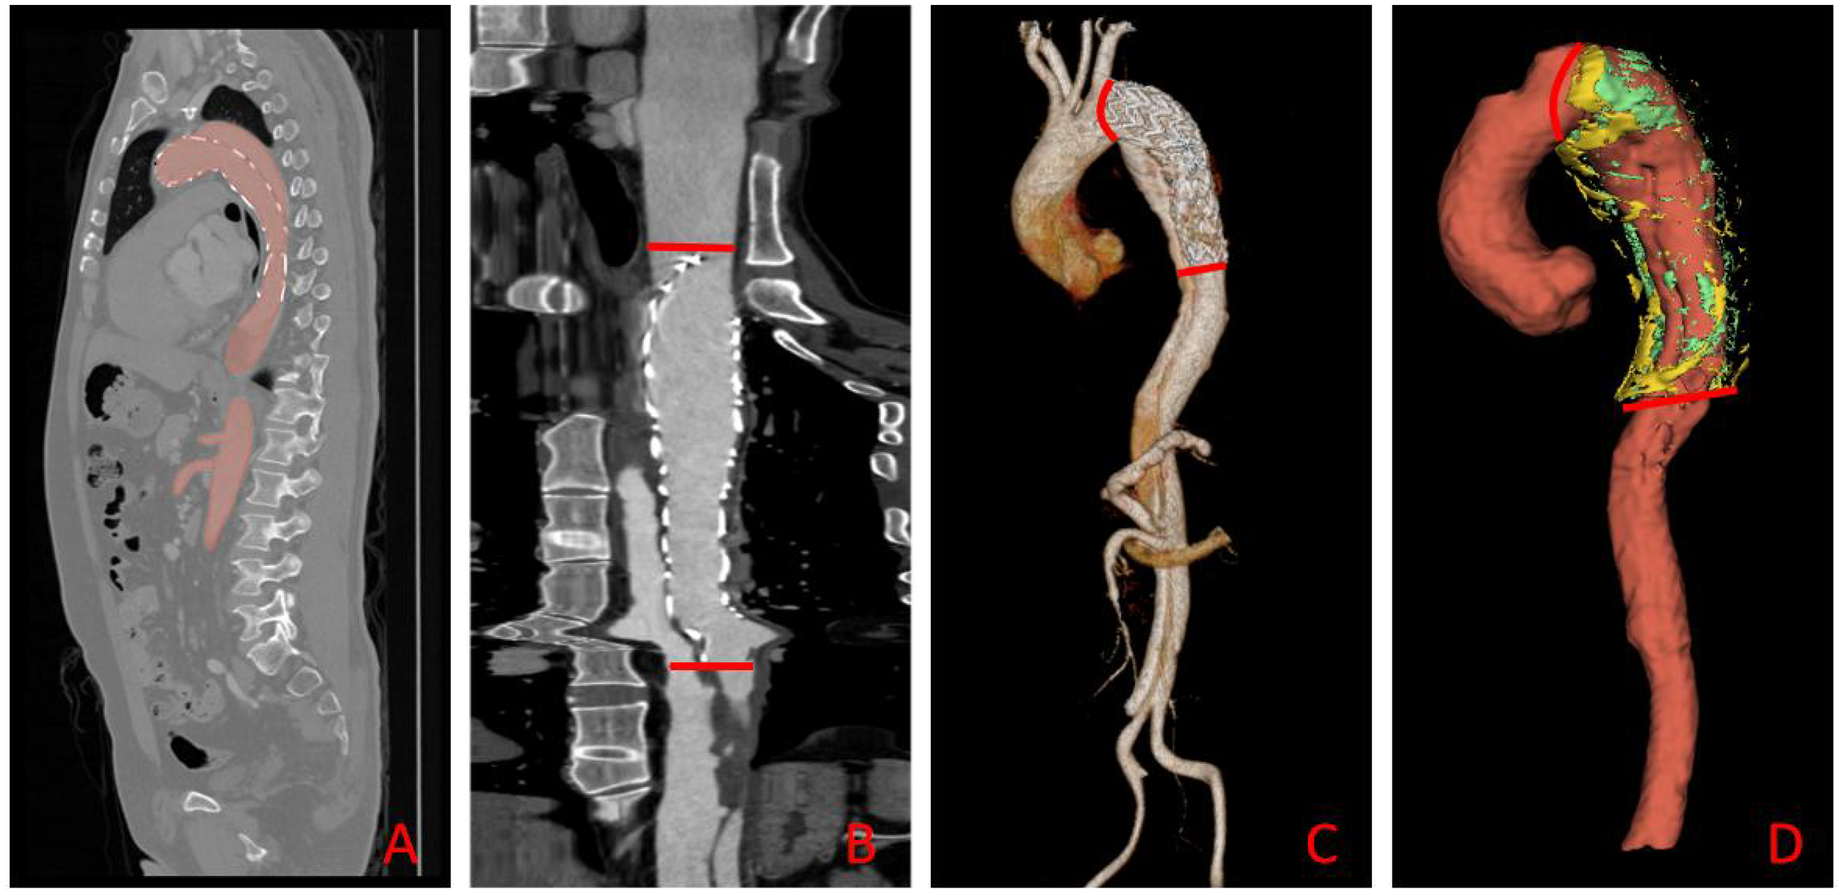

To improve segmentation efficiency and standardize post-operative analysis, we used the open-source, pre-trained TotalSegmenter model built on the nnU-Net framework (19, 20). The model automatically delineated the aorta—from the right coronary ostium to the iliac bifurcation—and perivascular adipose tissue (PVAT) on contrast-enhanced CT, as shown in Figure 3. Although TotalSegmenter has not been externally validated for PVAT segmentation in this specific dataset, it has been widely validated across multiple other datasets. To ensure the accuracy of the segmentation, all automatic masks were independently reviewed by two radiologists. Any discrepancies were resolved by a senior cardiovascular radiologist. Additionally, manual corrections were made around the endovascular stent grafts to exclude metal-induced artefacts, ensuring the integrity of the segmentation results.

Figure 3

Automated aortic segmentation, range selection, and 3-D visualization workflow. (A) Sagittal CT slice showing the automatically segmented aortic mask (red overlay); (B) straightened (centerline-reformatted) aorta; the segment between the two red bars defines the quantitative analysis range. (C) Three-dimensional surface rendering of the aorta, with the same proximal and distal limits (red bars) demarcating the analysis segment. (D) Composite 3-D rendering of the selected aortic segment and its surrounding PVAT: the aorta is displayed in red, HU close voxels in green, and HU distance voxels in yellow.

Starting from the outer aortic adventitia generated by TotalSegmentator, we applied two concentric 3-D dilations (radial offsets 2–5 mm and 10–12 mm) to define the proximal (HUclose) and distal (HUdistant) PVAT rings, respectively. Voxels with attenuation between −180 HU and −30 HU were retained to identify adipose tissue (21). This workflow was executed by a single Python batch script, ensuring identical radial offsets and density thresholds across all patients.

Two quantitative indices were derived: HUΔ = HUclose −HUdistant and HUratio = HUclose/HUdistant (17). The resulting PVAT masks are illustrated in Figure 4. Three-dimensional centreline extraction and visualisation of aortic dissection were performed with 3D Slicer and CREALIFE software (http://www.crealifemed.com) (22).

Figure 4

Multiplanar CT segmentation of perivascular adipose tissue (PVAT). (A) shows an axial (transverse) slice, (B) a coronal slice, and C a sagittal slice. The aortic lumen is delineated in red (aortic mask); PVAT immediately adjacent to the aortic wall is highlighted in green (HU close mask), while PVAT located farther from the wall is indicated in yellow (HU distance mask).